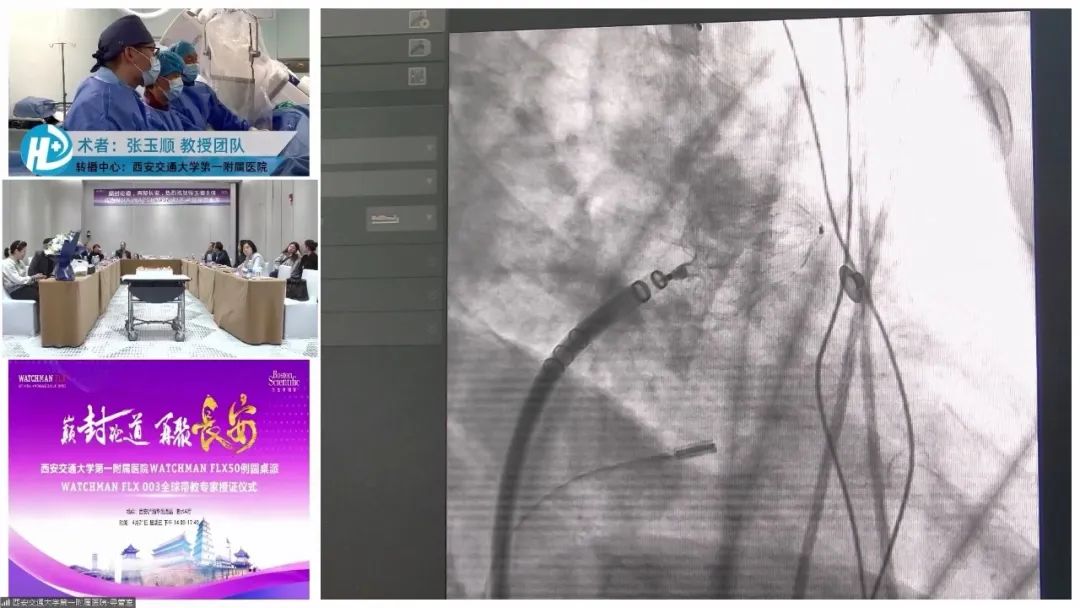

手术转播环节,张玉顺教授团队、谢学刚教授与宋治远教授联袂完成了一例WATCHMAN FLX 封堵器植入术,术后造影及经胸超声结果显示封堵器形态良好,无残余分流,封堵效果理想。

术后,西京医院刘海涛教授就“FLX的学习曲线很短,通常术者做完几例后就能很快上手,在开展了那么多左心耳封堵手术后,还有哪些问题?提醒术者什么?”等问题与宋志远教授进行互动。宋治远教授表示,任何一种封堵器都不可能十全十美,根据技术的不断更迭,器械也在不断更新升级中。从目前情况看,无论是封堵器的安全性,还是短的学习曲线等方面看,FLX是最好的一款封堵器械。在手术过程中个人分享的经验有两点,一是封堵伞选大不选小;二是注意封堵器释放的时候,根据病人情况选择具体方式,有的选择推鞘法,有的是推进法。

张玉顺教授荣获N03·WATCHMAN FLX 全球带教专家!

精彩的学术环节后,迎来本次活动的高光时刻——WATCHMAN FLX 003全球带教专家授证仪式。蒋世良教授、朱鲜阳教授共同为张玉顺教授颁发WATCHMAN FLX 003全球带教专家证书。